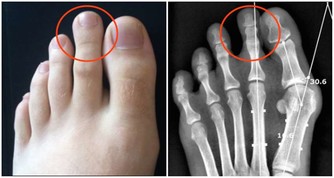

中醫師黃慧娟指出,造成痛風的主要原因為民眾經常食用高普林(Purine)食物,

像是海鮮、動物內臟、豆類等,促使體內尿酸過高,造成新陳代謝異常,

進而形成尿酸鹽結晶,沉積在關節內,造成關節疼痛及腫脹。